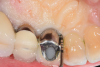

After local anesthesia was administered, full-thickness flaps were elevated from the buccal and lingual aspects of tooth No. 27 to the distobuccal and lingual aspects of tooth No. 31. Removal of granulomatous tissue from the implant site allowed visualization of a combination lesion with two walls at the distal and two to three walls at the mesial with a circumferential configuration on the lingual (Figure 12). The surface was initially treated with a 50% solution of citric acid for 30 seconds, which was burnished on with cotton pellets followed by thorough rinsing with sterile saline. This was followed by implantoplasty using 12-fluted followed by 30-fluted surgical-length finishing burs that provided access to the base of the defect. Because the crown was cemented, which obviated access, a matte-like surface could not be achieved; thus, the goal was to reduce the threads and remove the outer affected surface to expose fresh titanium (Figure 13). At this stage, the implant was wiped again with citric acid and rinsed with sterile saline.

Fig 13. Implantoplasty was completed. Some bleeding at the distal obscured one thread that was impossible to plasty. The surface was subsequently wiped with citric acid prior to grafting.

Figure 13